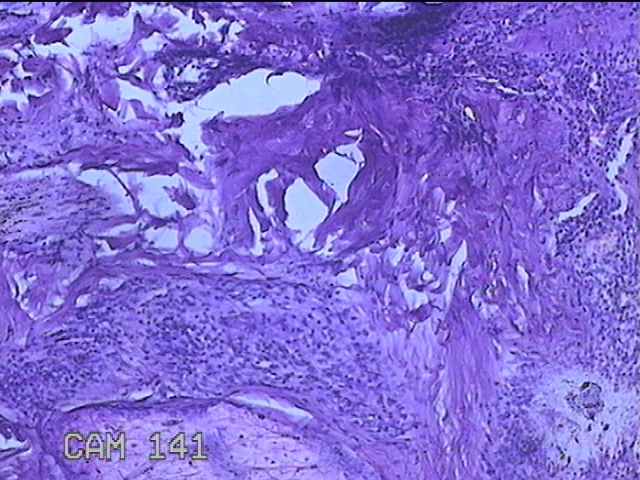

左侧臀部结节

性别

男

年龄

40岁

临床诊断

皮下结节

一般病史

发现左侧臀部结节1年余。

标本名称

大体所见

灰白粉红色组织1.3x0.8x0.3cm一块,表面带梭形皮肤1.3x0.8cm,皮下见结节1.3x1x0.7cm一个,切开结节呈实性,切面灰白粉红色,质软。

图3